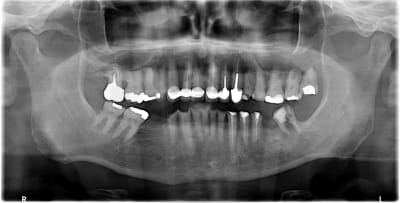

Ce patient se présente à moi pour poser 3 implants, et si possible redonner un peu d'esthétique à son sourire car ses incisives du bas sont trop "petites".

Je lui ai proposé d'extraire avant toute chose la 37 qui est condamnée et qui fausse l’étude de l’occlusion (en demandant de serrer je n'ai qu'un contact sur la 47 et la 37 (qui est algique et qui provoque un réflexe d'évitement). Vu les usures massives, je doute d'avoir qu’une composante erosive (ROG probable). Mais je préfère adresser pour la suite, n'ayant qu'une maigre expérience de ce genre de cas. Je connais dans les grandes lignes la théorie d'approche de ces plans de ttt (rehausser et tester la DVO avec une gouttière, puis des mock up et enfin des restaurations céramique collées type facette et table top) mais je n'en ai jamais réalisé.

Si tu lui enleves la 37 , tu pourras constater que la couronne de 17 ne va pas bien .

Il doit y avoir un decalage lateral dessus à tous les coups .

Tout ceci a été augmenté ou causé par un sur contact ant . Je dis ca pcq 13 12 11 ont ete faites sans reconstitutions , donc il y avait encore de la matiere . Pour solidariser je pense , à demander . C est donc qu il y avait deja dessus une parafonction d evitement de derriere .

Si la 17 est en fer ce serait elle la salope .

Si c est du zircon elle est plus recente et elle a du etre calée dans l occlusion deja pipée .

voila pourquoi je dis qu elle ne doit pas etre top dans tous les cas.

Et voila aussi pourquoi je dis tjs qu il faut tjs essayer de connaître l ordre des travaux deja effectués . pouvoir expliquer le passé permet d envisager l avenir . En tout cas c est plus facile de poser un diag sur la direction du calage a rechercher .

Très intéressant ton analyse comme toujours. De souvenir oui la 17 est en ferraille et bien ancienne

Les CR du bloc antr sup sont à étudier avec attention je pense.